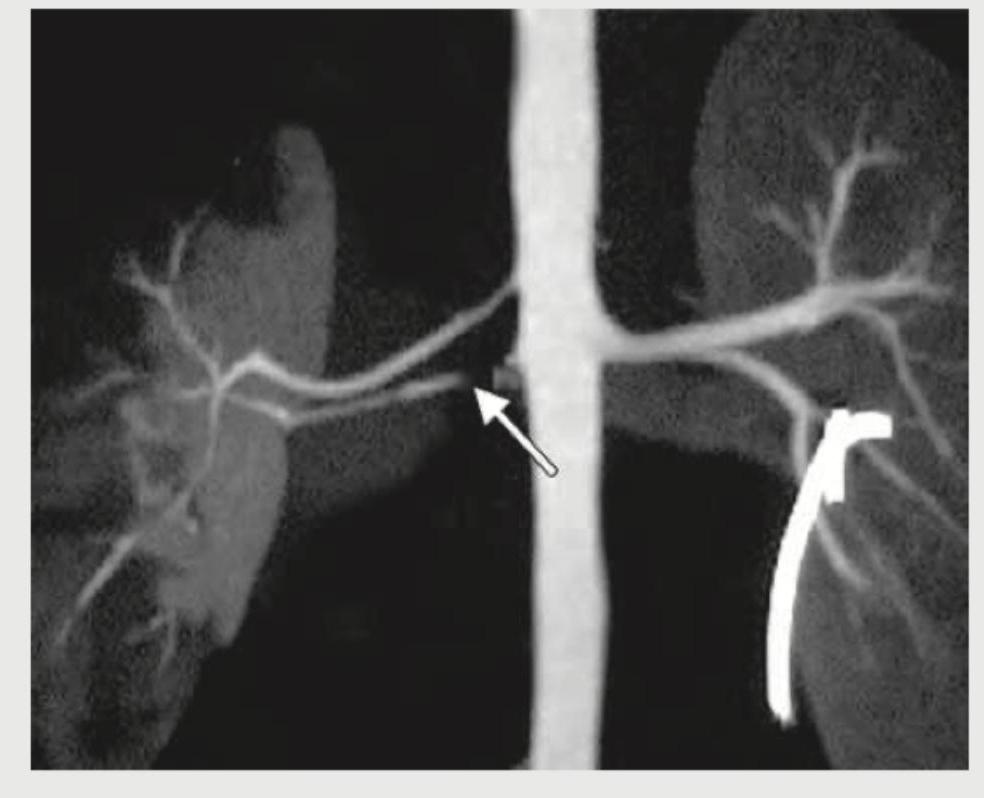

A 60-year-old hypertensive patient was showing poor response to three classes of antihypertensive drugs (ACE inhibitors, CCB and diuretics). Renal CT angiography was performed. What is the diagnosis?

Explanation: ***Renal artery stenosis*** - The image shows a **narrowing (stenosis)** of the right renal artery (indicated by the white arrow), which is consistent with the clinical presentation of **resistant hypertension** in a 60-year-old patient. - **Renal artery stenosis** leads to decreased blood flow to the kidney, activating the **renin-angiotensin-aldosterone system** and causing refractory hypertension. *Autosomal dominant polycystic kidneys* - This condition presents with numerous **cysts** in both kidneys, leading to their enlargement and impaired function, which would appear as multiple fluid-filled sacs on CT angiography, not arterial narrowing. - While ADPKD can cause hypertension, it is due to renal parenchymal disease and cyst growth, not primarily a focal arterial narrowing as seen. *Polyarteritis Nodosa* - This is a form of **vasculitis** that can affect medium-sized arteries, including renal arteries, causing **microaneurysms** and infarctions, but typically not a single, focal stenosis as depicted. - PAN is a systemic disease with other clinical features like fever, weight loss, and skin lesions, which are not mentioned. *Duplication of collecting duct* - This is a congenital anomaly affecting the **urinary collecting system**, not the renal vasculature. - It would involve two ureters draining a single kidney or a bifid collecting system, and would not explain resistant hypertension or the arterial narrowing seen.